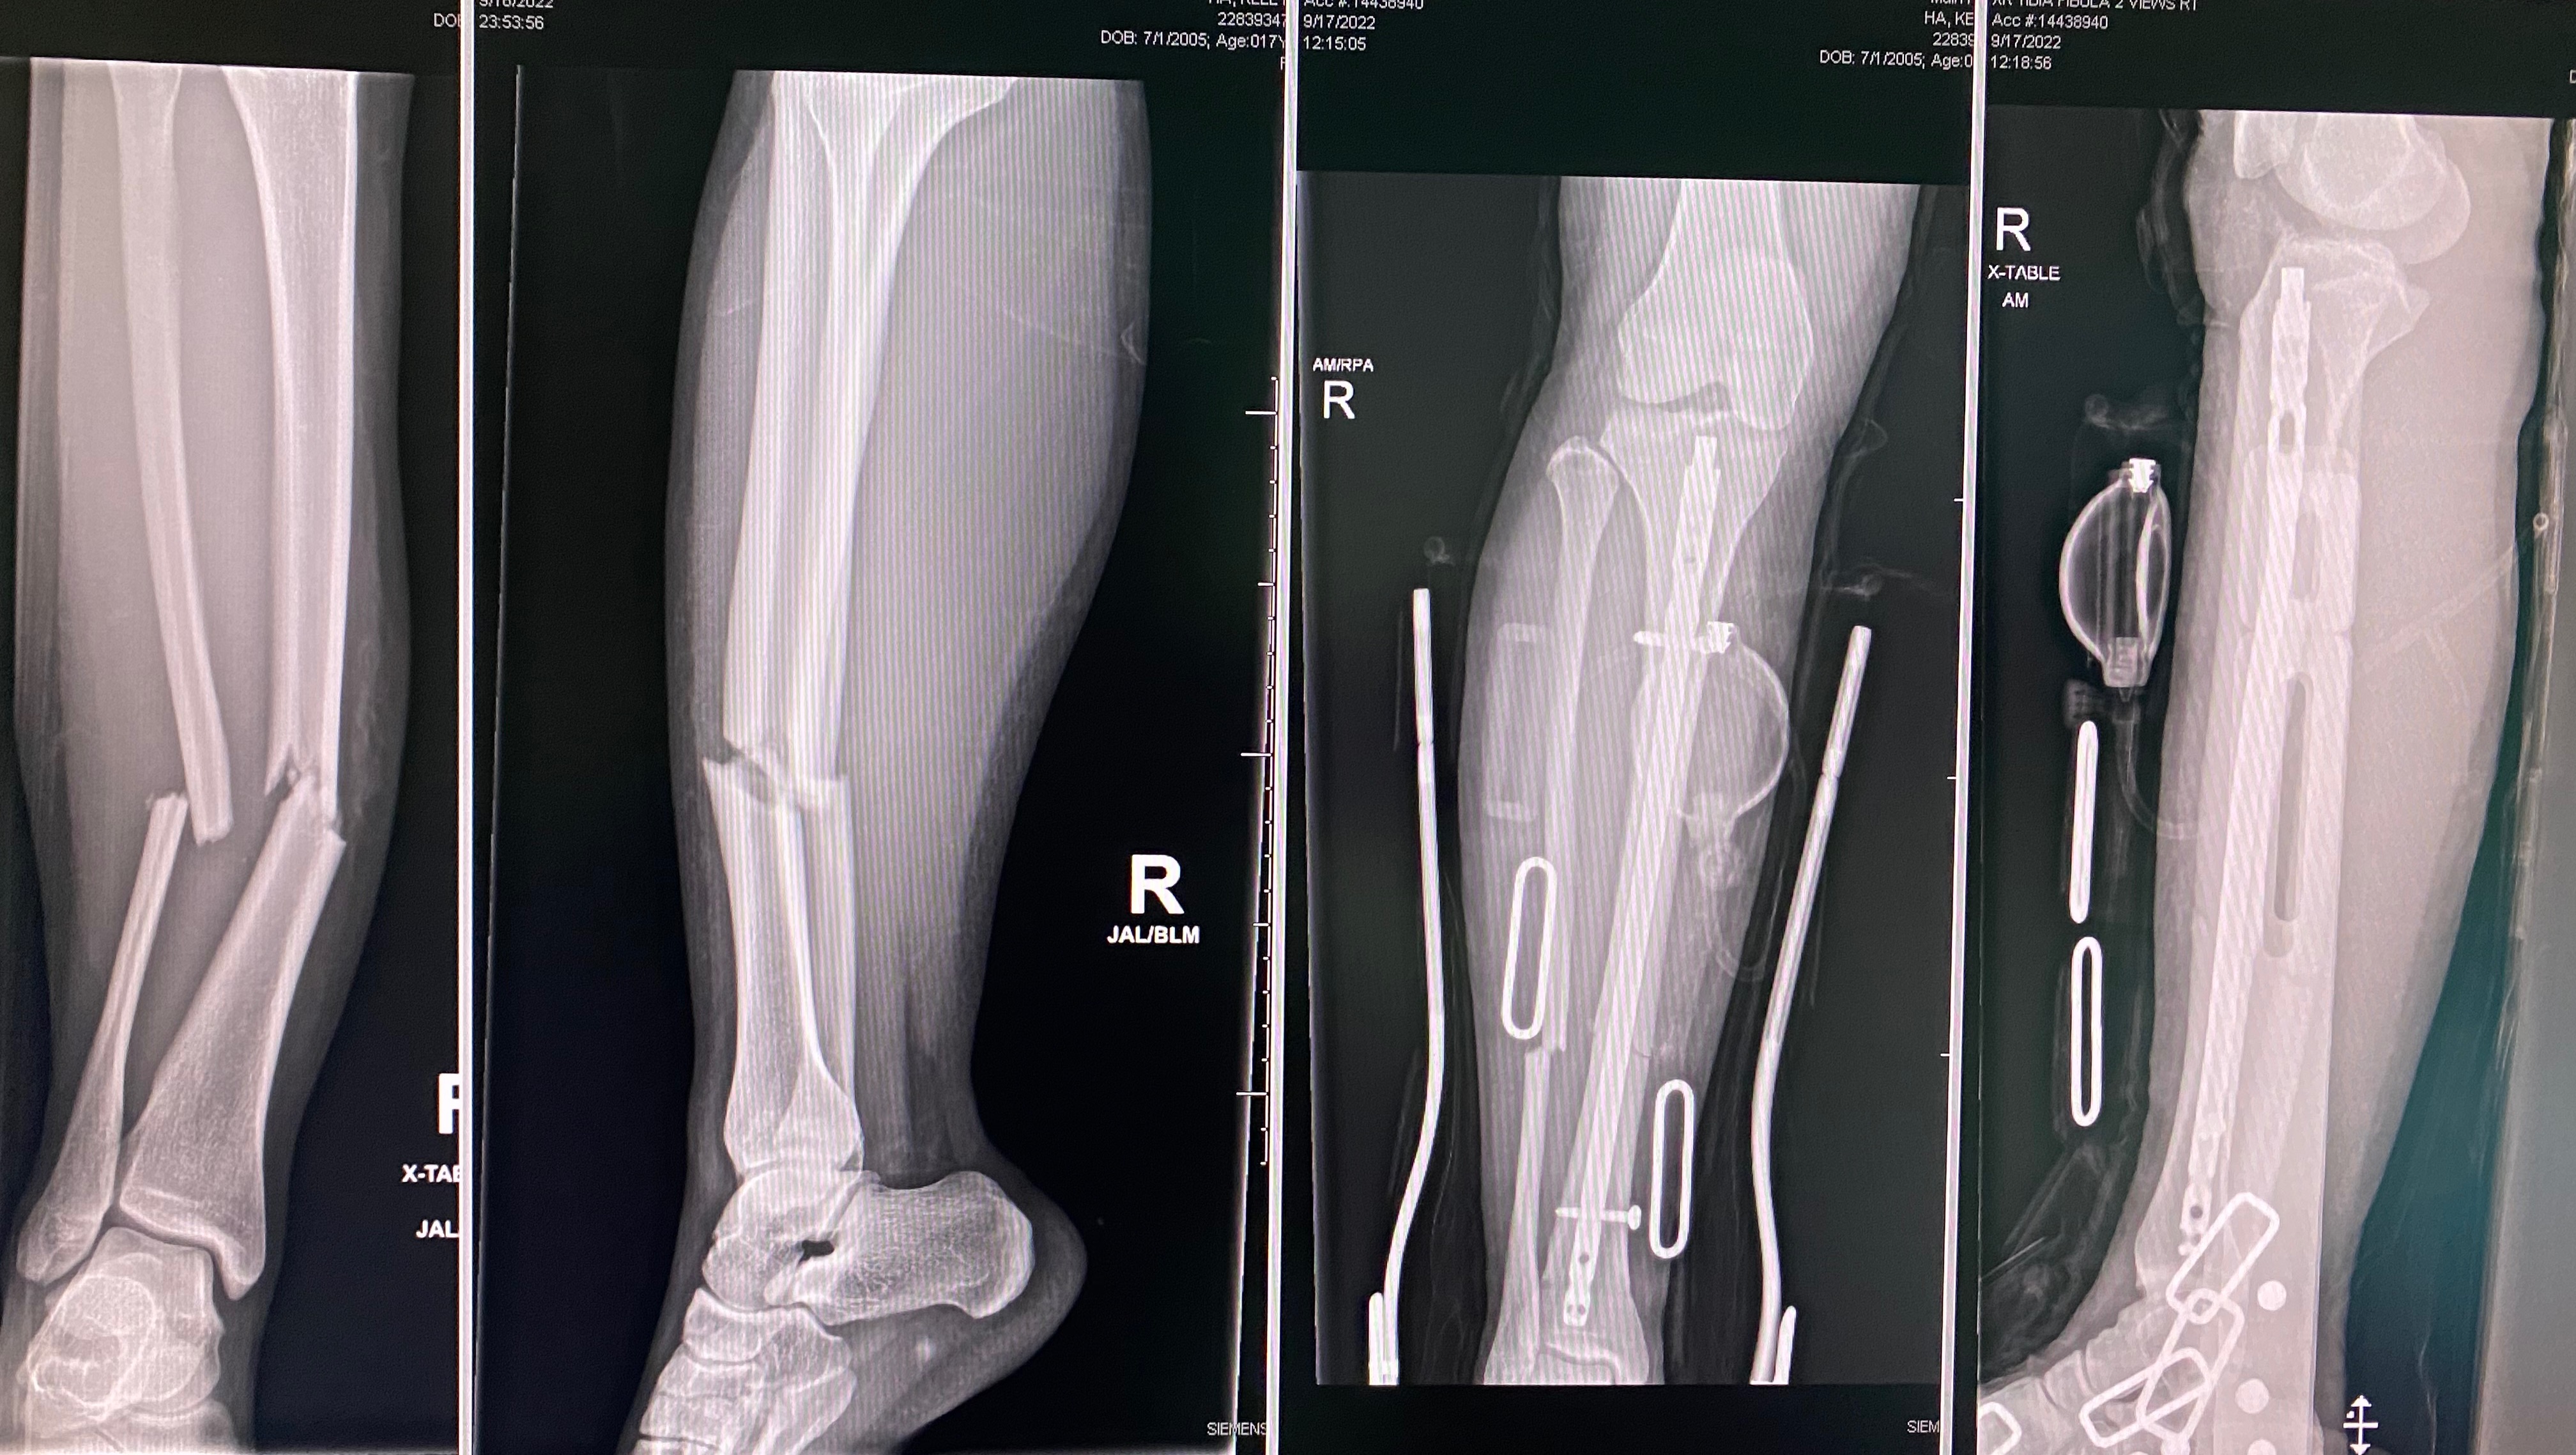

Fundraiser by Kelly Ha Tibial and Fibula Fracture Return To Sports After Fibula Fracture Tibia fractures treated surgically had a range of 12 weeks to 54 weeks for return to sport; Fractures treated without surgery ranged. In this video, i explain the process of returning to sports after a distal fibula/lateral malleolus fracture. It applies any time you break a bone,. For some fractures, patients who continue physical therapy and have good bone healing. Return To Sports After Fibula Fracture.

Figure 1 from Return to Sport Following Surgery for a Complicated Tibia Return To Sports After Fibula Fracture It applies any time you break a bone,. Return to sport is an important goal in treatment of ankle fractures in a sporting. For some fractures, patients who continue physical therapy and have good bone healing may be able to start running and return to sport. Early to unrestricted return to sport (5+ months after surgery) rehabilitation goals • gradual. Return To Sports After Fibula Fracture.